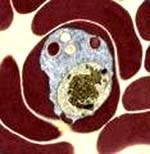

Báo cáo của Giampaolo Mezzabotta (Văn phòng WHO tại Việt Nam) cho biết, có 2 chủng lao mới là lao đa kháng thuốc và lao siêu đề kháng. Lao đa đề kháng (MRD-TB hay Multi Drug Resistance Tuberculosis) là một dạng bệnh lao nặng, thường có kết quả đàm dương tính, gây ra bởi vi khuẩn lao kháng tối thiểu hai loại thuốc kháng lao Rifampicin và Isoniazide). Thế giới ước tính trong 9.2 triệu người mắc bệnh lao mỗi năm, có khoảng 489 ngàn ca bị lao đa kháng thuốc, làm tử vong khoảng 120 ngàn người, trong đó Việt Nam có khoảng 6.421 ca (2.7%) và đã có khoảng 1.576 ca tử vong.

Lao siêu kháng thuốc là bệnh lao đa kháng được cộng thêm đề kháng với Fluoroquinolone và bất kỳ loại nào trong dòng thuốc tiêm hàng thứ hai (Amikacin, Kanamycin hoặc Capreomycin). Năm 2005, thế giới ước tính có khoảng 27 ngàn người mắc bệnh lao siêu kháng thuốc, trong đó có khoảng 16 ngàn người đã tử vong. Tại Việt Nam có khoảng 640 ca lao siêu kháng thuốc, đã khiến khoảng 384 người bị tử vong. Lao đa kháng thuốc đang là một thách thức lớn đối với y học bởi nó luôn luôn liên quan với tỷ lệ tử vong cao, nhất là khi bệnh kết hợp lao và nhiễm HIV (TB/HIV); đòi hỏi quy trình chẩn đoán và điều trị phức tạp và kéo dài thời gian. Các chuyên gia y tế khuyến cáo: MRD-TB là kẻ giết người thầm lặng vì vậy các quốc gia nên bắt đầu ngay cho việc nâng cấp quản lý có chương trình đối phó với lao đa đề kháng trước khi nó phát triển đến mức khó kiểm soát.

Theo ước tính của Tổ chức Y tế Thế giới (WHO), hiện nay trên thế giới có khoảng 50 triệu bệnh nhân có vi trùng lao kháng thuốc và khoảng 400.000 bệnh nhân lao thuộc loại lao đa kháng thuốc (kháng với hai loại thuốc chống lao chủ lực là INH và RMP). Nguyên nhân chủ yếu dẫn đến vi trùng lao kháng thuốc là do người bệnh không tuân thủ nghiêm ngặt và đầy đủ thời gian cũng như liều lượng thuốc của liệu trình điều trị bệnh. Trong những năm gần đây, WHO đã điều chế những loại thuốc kháng lao mới - thuốc kháng lao thế hệ thứ hai để điều trị bệnh lao kháng thuốc. Tuy nhiên, năm 2006 trên thế giới đã xuất hiện một loại bệnh lao mới - bệnh lao siêu kháng thuốc (XDR_ extensive drug resistant TB strains), đây là bệnh lao vừa kháng lại những thứ thuốc lao thế hệ thứ nhất và có thể kháng luôn một số thuốc kháng lao thế hệ thứ hai.

Một số báo cáo ở châu Phi cho biết loại “vi trùng lao siêu kháng thuốc” này thường phối hợp và đồng nhiễm với HIV/AIDS. Theo WHO, bệnh lao hiện nay là vấn đề sức khỏe của toàn nhân loại và mang tính khẩn cấp toàn cầu, với mỗi năm trên thế giới vẫn còn khoảng 2 triệu người mắc bệnh lao. Bệnh lao đang gia tăng trở lại với hình thức mới, nguy hiểm hơn do đại dịch HIV/AIDS. Nhưng lao là một bệnh có thể phòng ngừa và chữa được.